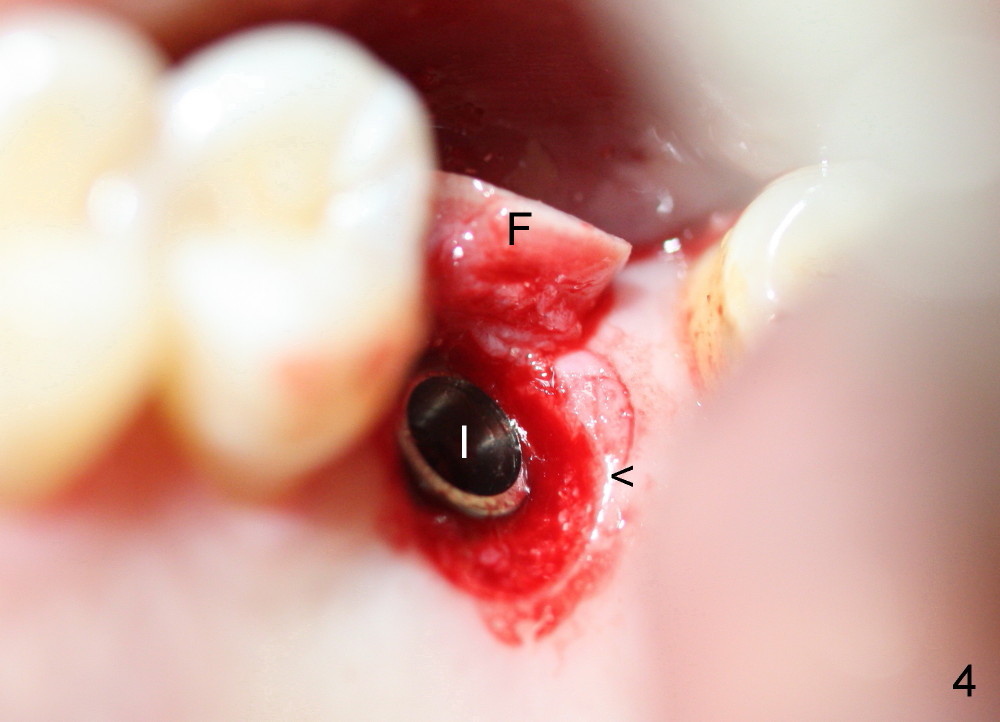

A 45-year-old man has lost the tooth #14 for a while (Fig.1); bone height is 5.4 mm. An extra wide and short implant is planned. Torus palatinus is large, suggesting that bone density should be high. A 6 mm tissue punch is chosen, but it is placed more palatal. If it were placed in the middle of the ridge, there would be no buccal keratinized gingiva (incision may avoid this issue). Additionally, the buccal portion of punch is made incomplete so that there is pedicle on the buccal side when the flap is raised (Fig.4,8: F). It is expected that the excess portion of keratinized tissue will form thick gingiva buccally. Osteotomy proves that bone is dense (Fig.2 (4.5x11 mm tap). Typical sinus lift is finished with placement of 6.4x6 mm (extra wide) bone-level implant (Fig.3, >55 Ncm). Following further torque, Fig.4 shows that the implant (I) is sub-gingival (<). Bitewings are taken to confirm that the implant plateau is at the crestal level (Fig.5,6 ^). PA shows sinus lift (Fig.7 *). The lingual aspect of the implant and healing abutment (H) is further bone grafted and covered by collagen dressing (Fig.8 *). The wound is protected with perio dressing. When the latter dislodges 7 days postop, the collagen dressing and bone graft are lost as well (Fig.10), while the buccal flap remains vital (Fig.9). The lingual exposed plateau should be able to heal normal. The collagen dressing should have been fixed in place by suture or as simple as a dental floss. There is mild nasal hemorrhage 1-2 days postop, possibly related to sinus membrane perforation and inability of Collagen Dressing to cover the perforation and contain the bone graft. When the patient returns for #9 implant placement in 3 weeks postop, the buccal flap reduces in size (Fig.11 *), while the palatal wound has healed with minimal exposure of the implant (Fig.12). Sinus graft remains in place 3 months postop (Fig.13); the buccal flap appears to have incorporated into a part of the gingiva (Fig.14). The bone density of the sinus lift appears to increase 10 days later when an abutment is placed (Fig.15 *). Although oral hygiene is pristine, there is apparent crestal bone resorption 12 months (Fig.16) and 20 months (Fig.17) post cementation, probably due to unfavorable crown/implant ratio and bruxism as well as pre-implantation bone loss (Fig.18,19). In contrast, an immediate implant in the same patient avoids pre- or post-implantation bone loss. In fact both the soft (Fig.20) and hard (Fig.21) tissues remain healthy 2 years 8 months post cementation. The sinus lift remains 3 years 8 months post cementation (Fig.22), while the crestal bone loss persists. The patients keeps complains of food impaction distal associated with bad smell 4 years 1 month post cementation. In fact the distal proximal contact is within normal limit. The bad smell is probably due to crestal bone loss (Fig.23 (pan), 24 (CT) *) and periimplantitis. Bone graft, PRF and Cytoplast membrane will be needed and fixed in place with long healing screw. When the patient returns for crown redo, he also reveals floss related gingival hemorrhage. There is pain associated with palatal sulcus probing with light gingiva erythema. Review of CT coronal section shows possible palatal (Fig.25 P) bone loss (*).